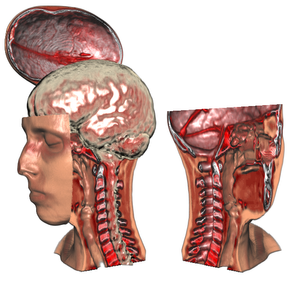

Exploded views are an illustration technique in which an object is partitioned into several segments. These segments are displaced to reveal otherwise hidden detail. In this paper we apply this concept to volumetric data in order to solve the general problem of occlusion. In many cases an object of interest is occluded by other structures which nonetheless provide important context information. While transparency or cutaways can be used to reveal a focus object, the problem of these techniques is that they remove parts of the information. Exploded views, on the other hand, do not suffer from this drawback. Our approach employs a force-based model: the volume is divided into a part configuration controlled by a number of forces and constraints. The focus object exerts an explosion force causing the parts to arrange according to the given constraints. We show that this novel and flexible approach allows for a wide variety of explosion-based visualizations including view-dependent explosions. Furthermore, we present a high-quality GPU-based volume ray casting algorithm for exploded views which allows rendering and interaction at several frames per second.Additional Files and Images

Exploded volume data view using part constraints

Exploded volume data view using part constraints